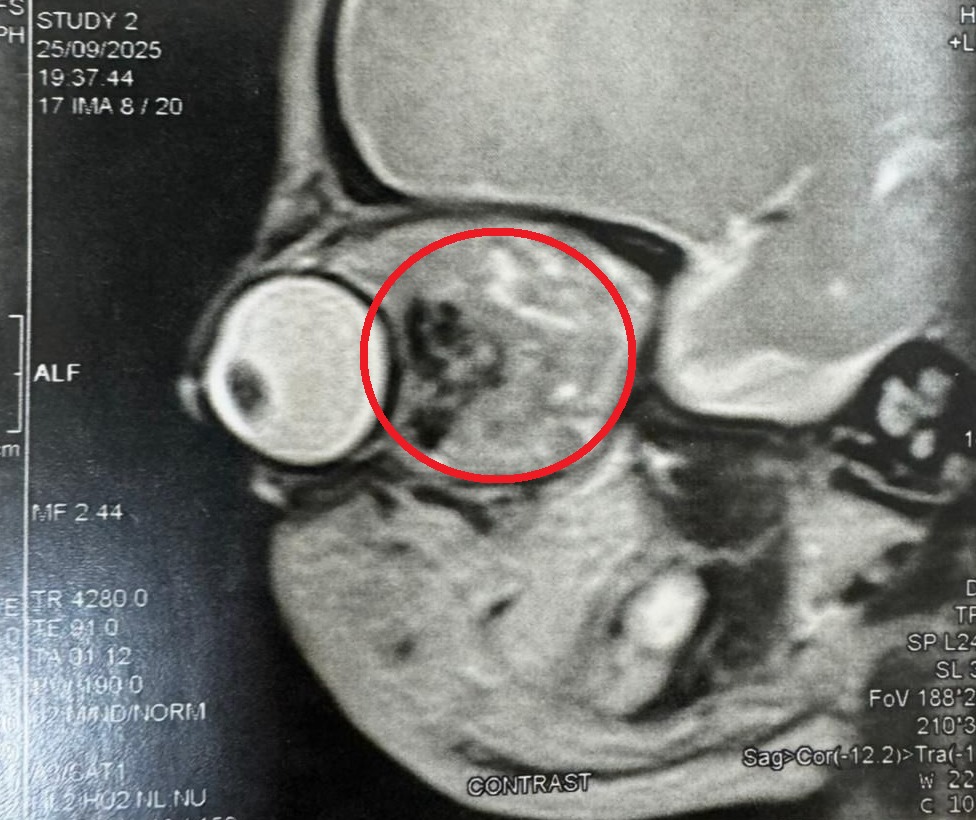

في إنجاز طبي غير مسبوق يعكس ريادة الطب المصري للأستاذ الدكتور أشرف عبد السلام ‏أستاذ جراحات محجر العين وتجميل العيون بكلية الطب جامعة عين شمس وقدرة كوادره على تحقيق المستحيل، نجح الأستاذ الدكتور أشرف عبد السلام، أستاذ جراحات محجر العين وتجميل العيون بكلية الطب جامعة عين شمس، في إنقاذ بصر طفل حديث الولادة لم يتجاوز عمره 24 ساعة، بعد إجرائه جراحة دقيقة لاستئصال ورم نادر من محجر العين، في عملية وُصفت بأنها الأولى من نوعها في الشرق الأوسط.

الجراحة أُجريت في ظروف دقيقة بالغة التعقيد، حيث اكتشف الفريق الطبي برئاسة الدكتور أشرف عبد السلام أن الورم بدأ في التكوّن أثناء وجود الجنين داخل رحم أمه، وهي حالة نادرة لا تُسجَّل إلا في عدد محدود للغاية على مستوى العالم.

ومع ظهور أعراض تورم العين فور الولادة، قرر الفريق الطبي التدخل الفوري لإنقاذ الطفل من فقدان بصره وربما عينه بالكامل خلال ساعاته الأولى في الحياة.

قال  الدكتور أشرف عبد السلام ‏أستاذ جراحات محجر العين وتجميل العيون بكلية الطب جامعة عين شمس إن الفريق دخل غرفة العمليات في سباق حقيقي مع الزمن، حيث استغرقت الجراحة ساعات طويلة من العمل المتواصل والتعامل المجهري مع أنسجة شديدة الحساسية خلف العين.

وأضاف أنه استعان بأحدث الميكروسكوبات الجراحية وتقنيات استئصال أورام محجر العين الدقيقة، وتمكن من إزالة الورم بالكامل مع الحفاظ الكامل على العصب البصري، مؤكدًا أن تلك اللحظة التي فتحت فيها عين الطفل بعد الجراحة وظهر العصب سليمًا كانت لحظة لا تُنسى.